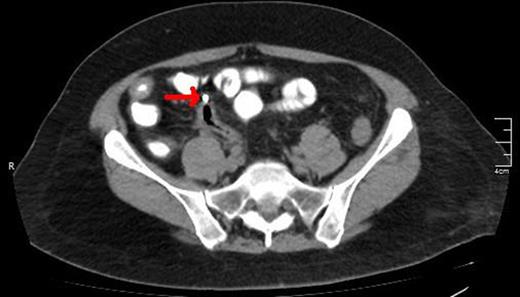

A CT scan showing the upper edge of the biliary stent perforating the antimesenteric surface of the sigmoid colon (red arrow).